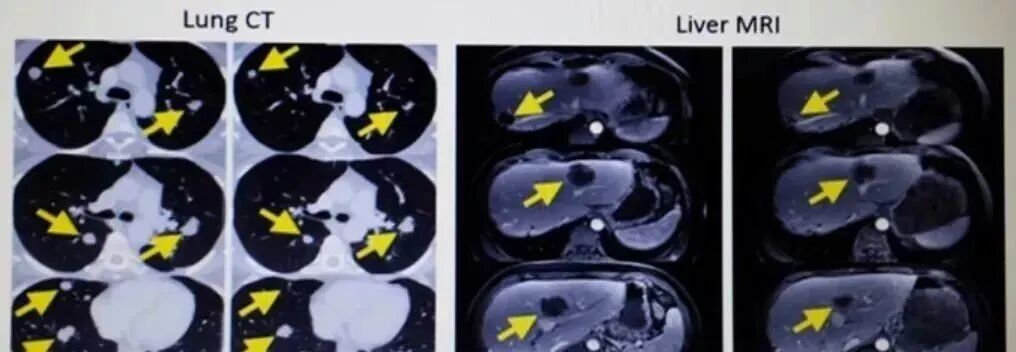

第二次回输超过1000亿个专门识别肿瘤细胞的免疫细胞战士浩浩荡荡的地进入了Melinda的体内。效果真的惊人!她全身肿瘤开始迅速缩小,体力恢复很快。

下面的对照图可以非常明显看到,第二次治疗前肺部布满的肿瘤,包括一些个头非常大的,第二次TIL细胞治疗20个月后复查,这些肿瘤都竟然都明显的缩小了。